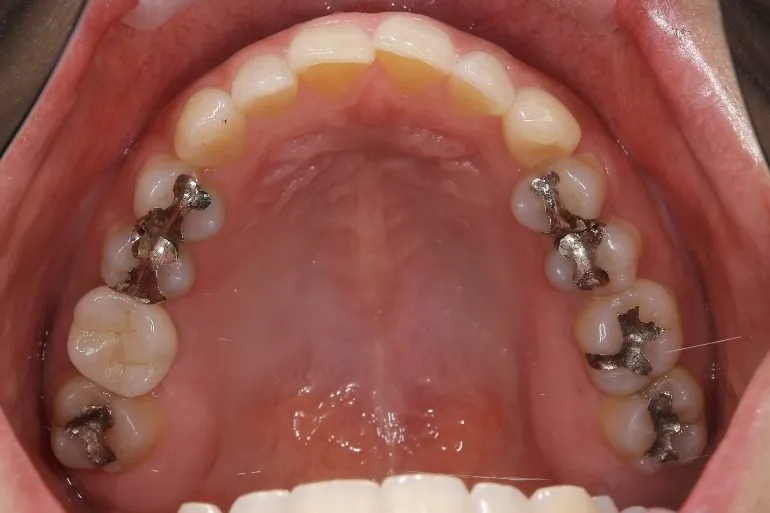

インプラント症例

【症例1】

治療名

インプラント治療

治療説明

インプラント治療とその他の補綴物による修復を行いました。

治療期間

1年

副作用・リスク

手術中に神経や血管を傷付ける可能性があります。痛み、腫れ、出血があります。インプラントの初期固定が取れない場合は、治療期間が長引いたり、すぐに仮歯を装着できない場合があります。

料金

¥3,135,000(税込)

インプラントのみ